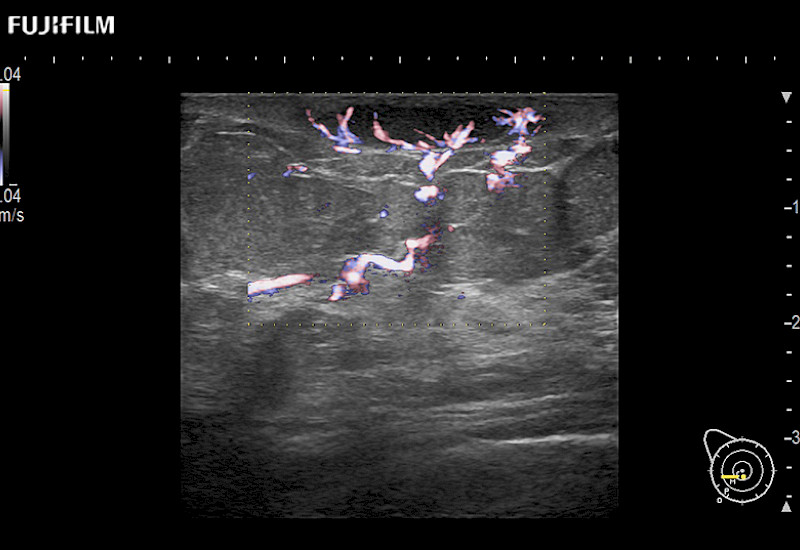

For precise surgical oncology ultrasound imaging, Fujifilm Healthcare offers premium level solutions that include:

Extraordinary high-resolution digital imaging

Exceptional transducers

for use during open and laparoscopic procedures: Tumor localization & staging, Ablation, Resection, Biopsy, Transplant, Abdominal exploration, Robotic surgery

Multi-Parametric imaging modalities

Our dedication to Surgical Oncology allows us to offer superior image quality, outstanding system reliability and intuitive use of cutting edge technology.